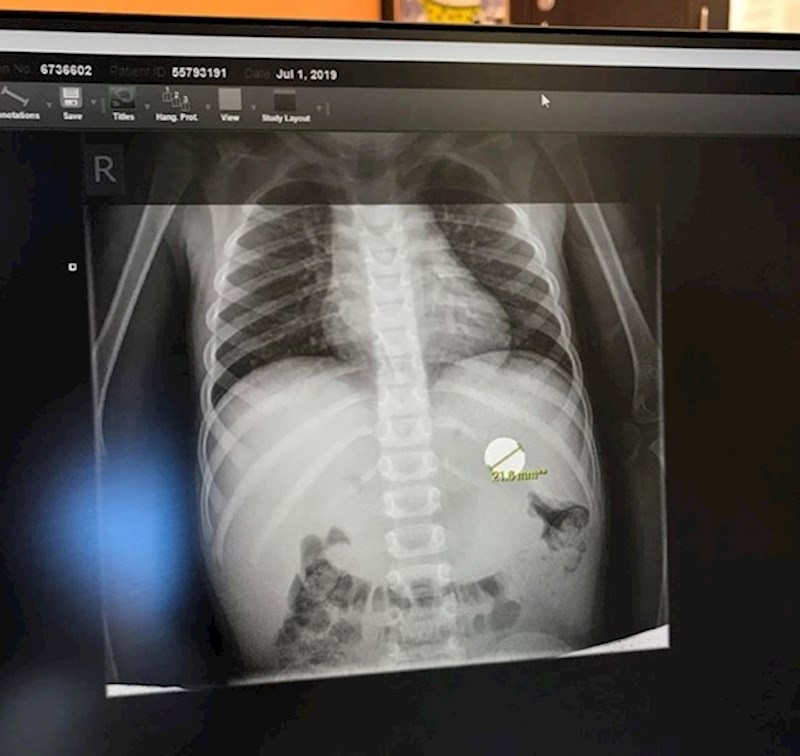

16. "Moj sin je pojeo novčić."